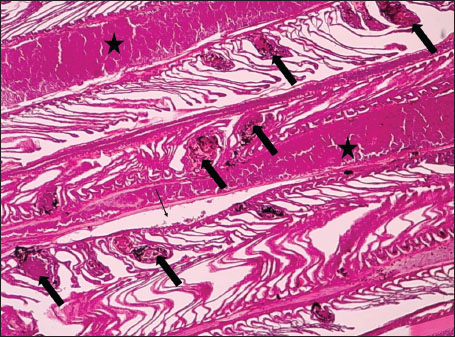

ABSTRACTBackground: The Mediterranean Sea has undergone significant ecological changes in recent decades, partly due to the introduction of non-native species. Lagocephalus sceleratus is an invasive Lessepsian species widely distributed in the Mediterranean, increasingly abundant along the Libyan coast, and potentially exposed to chronic environmental stressors. This species represents an important model for baseline pathological assessment in newly colonized marine environments. Aim: This study provides a descriptive histopathological assessment of kidney and gill tissues in adult L. sceleratus to document baseline tissue alterations without inferring direct environmental or pollution-related causation. Methods: A total of 150 adult specimens were collected from four Libyan coastal locations. Tissues were processed using standard histological techniques and evaluated semi-quantitatively (+, ++, +++) for lesion severity. Lesion severity grades were converted into ordinal numerical data and summarized using descriptive statistical approaches only. Results: Kidney tissues exhibited tubular degeneration, Bowman’s capsule dilatation, vascular congestion, extensive melanomacrophage centers (MMCs), and inflammatory lesions. Gill tissues showed disorganization of secondary lamellae, epithelial hyperplasia, edema, aneurysmal dilatations, vascular congestion, and MMC proliferation, some of which were associated with histologically observed parasitic structures. Conclusion: The observed alterations represent descriptive baseline tissue changes and should not be interpreted as direct evidence of pollution or specific environmental stressors. These findings provide reference data for future comparative pathological and ecological studies. Keywords: Lagocephalus sceleratus, Kidney, Gills, Histopathology, Melanomacrophage centers, Invasive species, Mediterranean Sea. IntroductionIn recent decades, the Mediterranean Sea has undergone profound ecological changes driven by the arrival and establishment of non-native marine species. Among these, Lagocephalus sceleratus has emerged as one of the most impactful Lessepsian migrants, due to its rapid geographic expansion, high ecological adaptability, and the presence of the potent neurotoxin tetrodotoxin in its tissues. This species has been widely documented to alter local fish communities, affect fisheries, and pose public health risks, making it an important target for biological and environmental assessment across the region (Katikou et al., 2022; Christidis et al., 2024). Fish are widely recognized as sensitive biological organisms in aquatic ecosystems, particularly in coastal habitats that are exposed to anthropogenic pressures such as industrial effluents, agricultural runoff, and untreated wastewater (Pinna et al., 2023). Among fish organs, the gills and kidneys are commonly regarded as sensitive to environmental stress, as they respond to physiological and pathological changes under environmentally suboptimal conditions. The gills, due to their large surface area and continuous exposure to surrounding water, are often the first tissues to exhibit structural alterations when fish encounter pollutants (Shahid et al., 2022). Histopathological changes in gills observed in polluted environments include epithelial lifting, lamellar fusion, hyperplasia, increased mucous cell density, and focal necrosis, which collectively reflect early physiological stress and potential compromise of respiratory function (Osman, 2010; Shahid et al., 2022). Similarly, the kidneys play crucial roles in osmoregulation, excretion of metabolic waste, and detoxification, making them highly vulnerable to chronic or systemic toxic effects (Wahidi et al., 2025). Documented renal lesions associated with chemical exposure include tubular deterioration, glomerular shrinkage, interstitial edema, and infiltration of inflammatory cells. These structural alterations often coincide with underlying biochemical disruptions, such as oxidative stress, impaired detoxification pathways, and activation of apoptotic mechanisms (Bernet et al., 1999; Authman, 2015). Despite the growing body of research on the ecological and toxicological implications of L. sceleratus, detailed histopathological assessments of this species remain scarce, especially in the southern Mediterranean basin, where environmental conditions and pollution profiles may differ from those in other regions. To date, detailed tissue-level studies of L. sceleratus from the southern Mediterranean are lacking, which limits the understanding of how this invasive species responds physiologically to local environmental stressors (Shakman et al., 2019; Ulman et al., 2021; Mohmmed et al., 2023). Accordingly, the present study aims to provide a comprehensive descriptive evaluation of histopathological changes in the kidneys and gills of L. sceleratus. The study is designed as a baseline histopathological assessment, focusing on tissue-level alterations without establishing causal links to environmental pollution or physicochemical stressors. By documenting structural aberrations and pathological features, this study contributes reference data for future monitoring and comparative studies in Mediterranean coastal ecosystems. Materials and MethodsSample designA total of 150 adult specimens of L. sceleratus, including both sexes, were collected from four Libyan coastal locations: Talamitha (n=39), Susah (n=34), Ain El-Ghazala (n=30), and Khalij Al-Bambah (n=47). Fish ranged in total length from 51 to 66 cm and in weight from 1.5 to 3.5 kg. Only apparently healthy adults were included, while juveniles were excluded to avoid age-related histopathological variation. Sampling was conducted opportunistically with assistance from local fishermen. All specimens were collected within a comparable seasonal window to minimize seasonal histopathological variability. Sex was recorded when possible; however, sex-based histopathological comparisons were not performed, as this was beyond the descriptive scope of the study. Fish were transported on ice at +4°C and examined in the Pathology Laboratory, Faculty of Veterinary Medicine, Omar Al-Mukhtar University (Mohmmed et al., 2023). Specimens were collected from a range of depths (0.5–70 m), with the majority from shallow waters (<10 m) and a subset (approximately 50 fish) from deeper locations (>30 m). Environmental physicochemical parameters such as temperature, salinity, and dissolved oxygen were not measured; therefore, no direct associations between histopathological findings and environmental variables were assessed. Tissue processing and histopathological examinationTissue specimens were fixed in 10% neutral buffered formalin for 24 hours. Following fixation, the samples were transferred to 70% ethanol for storage at room temperature. Subsequently, the tissues were processed for routine histopathological examination following standard procedures (Paul and Chanda, 2017). Paraffin embedding was performed, and 5 µm-thick sections were prepared using a microtome. Sections were stained with hematoxylin and eosin (H&E) and examined under a light microscope. Photomicrographs of representative lesions were captured using a high-resolution digital camera. Histopathological alterations were evaluated using a semi-quantitative scoring system adapted from Hose et al. (1996), Moshaie-Nezhad et al. (2021), and Alshailabi et al. (2023), where lesion severity was graded as mild (+), moderate (++), or severe (+++). Lesion severity grades (+, ++, +++) were converted into ordinal numerical values (1–3) for descriptive summarization of lesion severity. Due to the descriptive baseline nature of the study and the absence of a reference control group, inferential statistical comparisons were not emphasized or applied. Lesion severity scores were therefore summarized descriptively to avoid overinterpretation of the findings. Scoring was performed independently by two experienced observers, and representative lesions were confirmed across three sections per organ to ensure consistency. Tissues with visible parasitic structures were described separately from non-parasitized tissues to avoid conflating parasite-associated lesions with non-specific tissue alterations. The functional implications of the observed lesions were interpreted in accordance with Flores-Lopes and Thomaz (2011). Ethical approvalAll animal experiments conducted in this study were approved by the Ministry of Higher Education & Scientific Research and the Libyan National Committee for Biosafety & Bioethics, Libya. All procedures were performed in accordance with the relevant ethical guidelines, with session number 21/CH/25, dated 26/05/2021. ResultsHistopathological examination of the kidneyHistopathological examination of the kidney tissues of L. sceleratus revealed multiple alterations. Prominent melanomacrophage centers (MMCs), necrotic areas, dilatation of Bowman’s capsules, and vacuolar degeneration were observed (Fig. 1), associated with interstitial lymphohematopoietic tissue (Fig. 2). Dilated and congested blood vessels and extensive MMCs were also noted (Fig. 3). Renal degeneration surrounding lymphohematopoietic tissue, large clusters of MMCs, and thickened, congested vessel walls within fibrotic areas were evident (Fig. 4). Atrophic renal degeneration with necrotic and vacuolar changes was observed (Fig. 5). Severe inflammatory infiltration of lymphatic cells and granulomas with necrotic centers, surrounded by fibrous tissue, was detected (Figs. 6–7).

Fig. 7. Histopathology of the kidney in an adult L. sceleratus showed the atrophic renal degeneration (stars), dilatation of Bowman’s capsules (thick arrows), and a granuloma (head arrow). ×400 H&E. Histopathological examination of the gillsThe gill sections of adult L. sceleratus exhibited multiple structural alterations. Secondary lamellae showed marked disorganization, while gill filaments displayed club-shaped deformities and occasional aneurysmal dilatations (Fig. 8). Vascular congestion with telangiectatic changes and proliferation of MMCs were also observed (Figs. 9–10). Edematous changes in primary lamellae, separation of the epithelial layer, lamellar aneurysms, and epithelial hyperplasia were documented (Figs. 10–11). Focal damage to secondary lamellae, disruption of lamellar architecture, presence of lamellar aneurysms, and unidentified parasitic structures were observed (Fig. 12). Pronounced vascular congestion and dilatation of lamellae due to red blood cell accumulation were noted (Fig. 13).

Fig. 8. Histopathology of the gills in an adult L. sceleratus showing disorganization of secondary lamellae (thick arrows), club-shaped filament deformities with aneurysms (thin arrows), and congestion/telangiectasia in filament vessels (stars). ×40 H&E.

Fig. 9. Histopathology of the gills in an adult L. sceleratus showing the disorganized secondary lamellae (thick arrows), MMCs (thin arrows), and vascular congestion/telangiectasia in filaments (stars). ×40 H&E.

Fig. 10. Histopathology of the gills in an adult L. sceleratus showing the edema in primary lamellae and epithelial detachment (thin arrows), lamellar aneurysm with MMCs (thick arrows), and congestion/telangiectasia (stars). ×40 H&E.